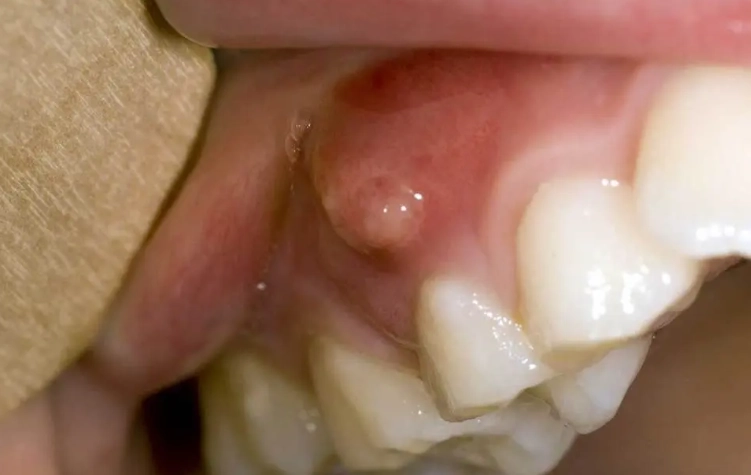

Mucocele (Mucous Cyst)

This is probably the champion of painless oral bumps. A mucocele is a tiny, fluid-filled sac that forms when a small salivary gland duct gets blocked or damaged (often from accidentally biting your cheek or lip). It's like a little blister of saliva trapped under the surface. What it feels/looks like: It's usually soft, smooth, and bluish or translucent. It can appear to change size, sometimes shrinking and then filling up again. You'll commonly find it on the inner lip, the floor of the mouth (where it's called a ranula if it's larger), or the inner cheek. It's completely painless but can be annoying.